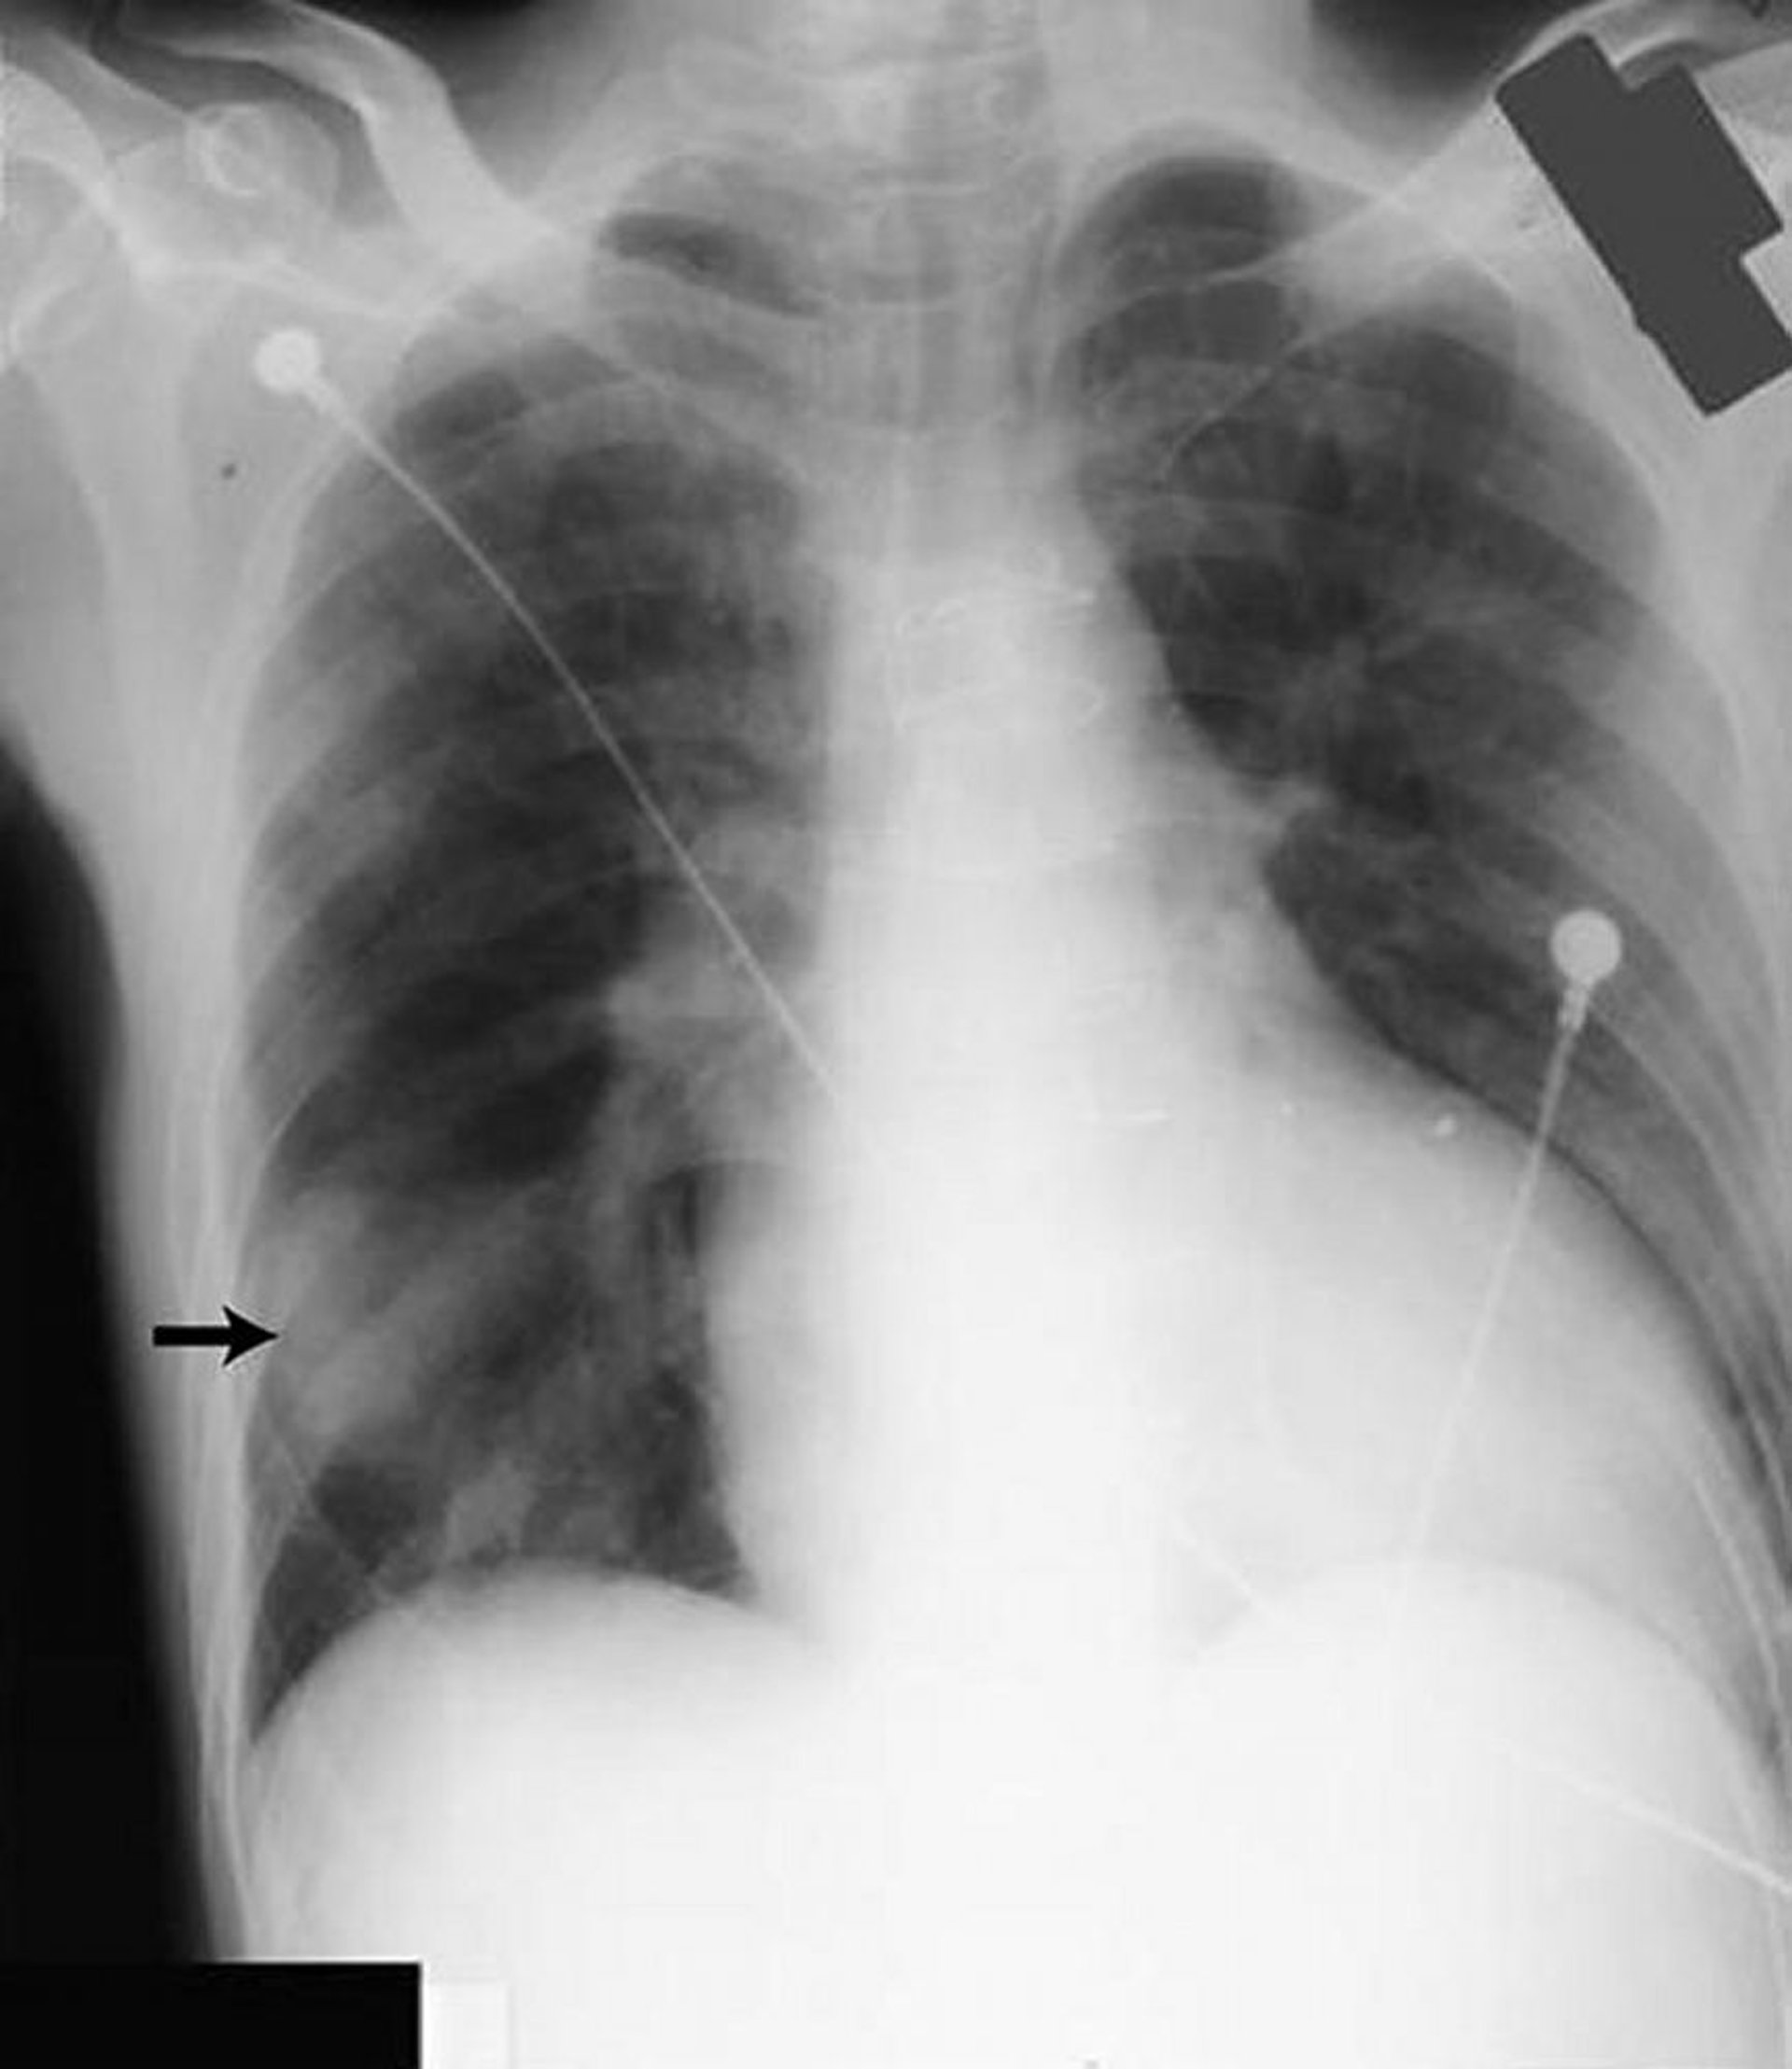

Легочные псевдоопухоли

Затемнение в нижней части правого легкого (стрелка) напоминает плотную опухоль, но образовано жидкостью, скопившейся в косой щели у пациента с сердечной недостаточностью.